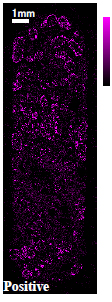

カプセル剤タイプ薬の断面についてTOF-SIMSによる質量イメージング分析を行いました。断面加工を行い、薬剤全体(約7mm×20mm)とその内部の顆粒一粒(約500μmΦ)に着目したイメージング事例をご紹介します。

光学顕微鏡像とTOF-SIMSイメージング

| 光学顕微鏡 | ●成分A | ■成分B | ▼成分C | |

●成分A:イブプロフェン

■成分B:デキストロメトルファン臭化水素酸塩水和物

▼成分C:無水カフェイン